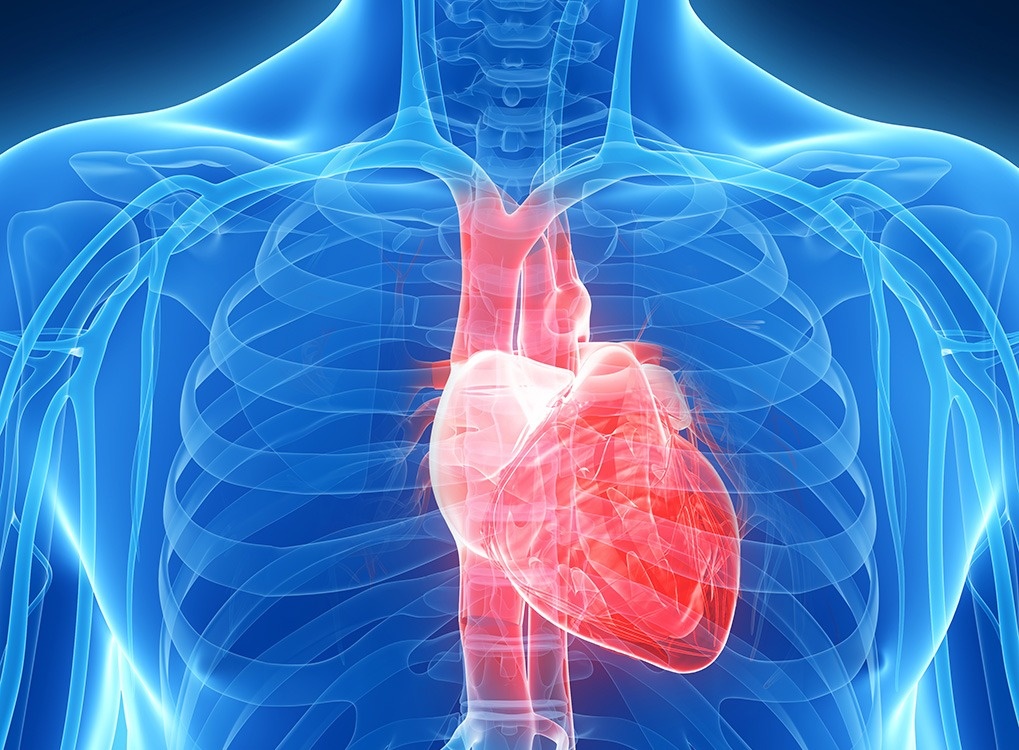

Анатомия сердца: Визуальные примеры и объяснения